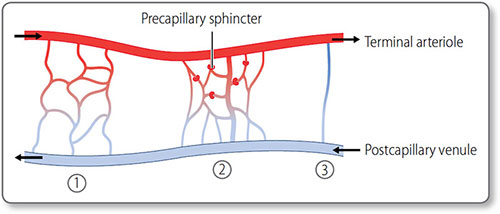

The microcirculation

The microcirculation is the functional unit of small vessels perfusing an organ or tissue (Figure 1.14). It consists of the:

Figure 1.14: The microcirculation. ①, The simple branched microcirculation architecture present in most tissues. ②, Central metarteriole, a thoroughfare channel with branching capillaries. ③, Direct atrioventricular anastomosis found in cutaneous tissues.

- Capillary bed

- Post-capillary venules

- Metarterioles, which bypass the capillary bed.

Microcirculation is regulated by terminal arteriolar tone, extrinsically by sympathetic innervation, and intrinsically, via autoregulation.

Precapillary sphincters These rings of vascular smooth muscle encircle the entrance to capillary beds. They control whether blood enters that bed or is shunted via metarterioles to post-capillary venules.